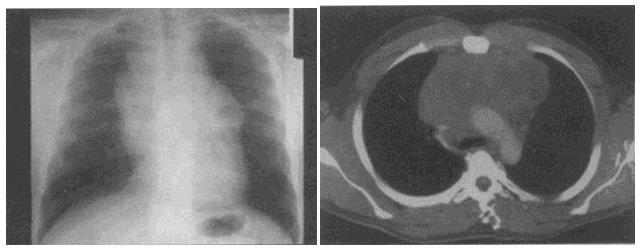

患者男,17岁,发现颈部肿块1个月,胸片检查、CT检查如图,最可能的诊断为()。

A、胸腺瘤

B、畸胎瘤

C、淋巴瘤

D、胸内甲状腺瘤

E、囊状淋巴管瘤

C